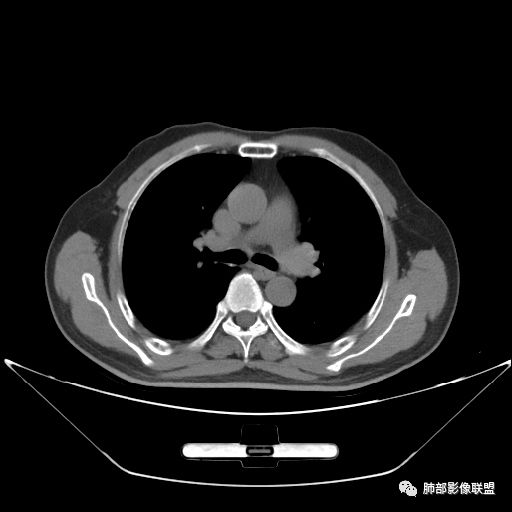

住院4天后行胸部增强CT

静脉期